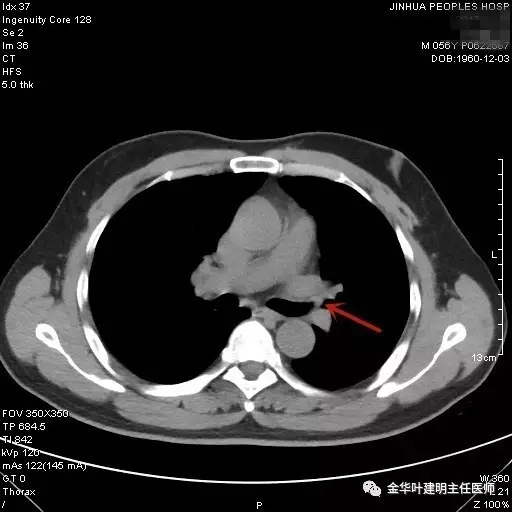

图二示:纵隔窗左肺上叶开口处新生物,相对肺窗稍明显